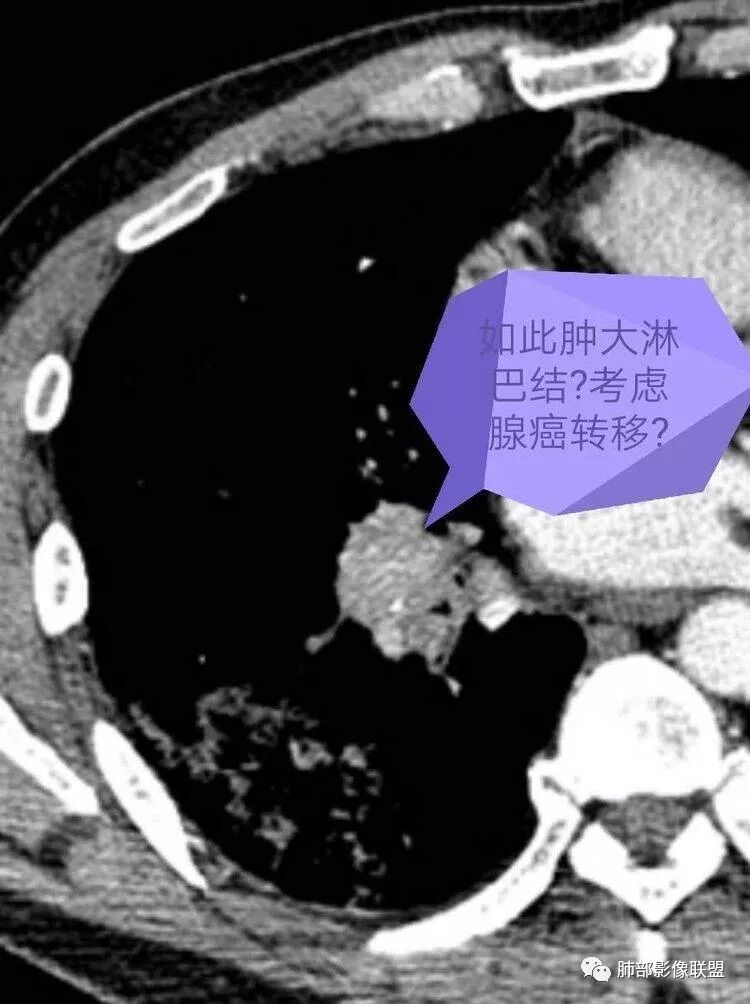

但是问题来了:淋巴结

右肺门区淋巴结增大,融合,密度均匀,均匀强化

符合这个特点的:结核?淋巴瘤?转移瘤?

淋巴结我觉得目前的特点:淋巴瘤?结核?

我一直以为是二元的,我觉得特别淋巴结里面又有钙化灶,我的想法肺部就是炎性病变,因为很典型的分布符合气道来源炎性病变,但是淋巴结是独立出来的,里面有钙化灶怀疑结核可能。

南边:当时看淋巴结该不该一元论?一元论该怎么考虑?因为右下肺病变确实没有恶性特点,所以还是考虑二元论。因为薄层CT确实有点状钙化,当时考虑结核可能性大,淋巴结确实涉及少了。